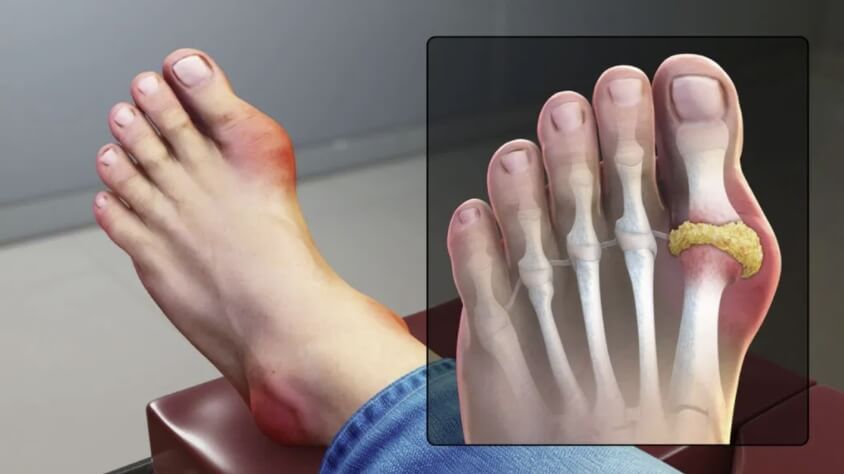

통풍은 요산이 너무 많아져서 혈액 내에 결정으로 축적됨으로써 발생하는 대사성 질환입니다. 요산은 일반적으로 신장을 통해 체내에서 배출되지만, 신장 기능이 저하되거나, 요산 생성이 과다한 경우에는 요산이 혈액 내에 축적되어 결정으로 형성됩니다. 이 결정이 관절 부위에 쌓이면 염증이 발생하여 통풍이 발생합니다. 따라서 상당히 고통스러운 통풍에 대해 보다 자세히 알아보기 위하여 원인, 증상, 치료방법 등을 자세히 알아보겠습니다.

염증

급성 통풍 발작은 관절 내부에서 염증이 발생합니다. 이는 염증을 일으키는 화학 물질이 적출물로 발적 주위에 축적되기 때문입니다. 염증은 일반적으로 통증, 붓기, 붉어짐 등을 초래할 수 있습니다.

발적

발적 부위는 붉고 따끔거리며, 적출물로 인해 부어오를 수 있습니다. 이러한 발적은 대개 발작이 발생하는 부위에 나타나며, 발적이 심한 경우 걷는 것이 어려울 수 있습니다.